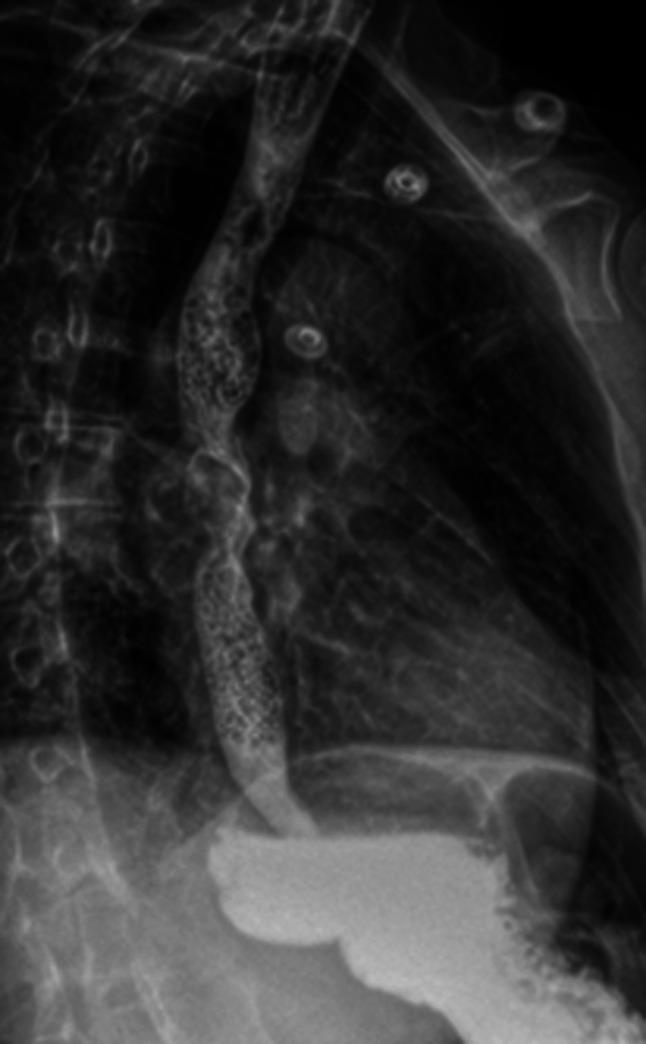

Esophageal diverticulum (ED) is a rare condition with a clinical presentation that can be variable. Esophageal diverticulum has been associated with motility disorders; however, the association with mid-ED is less clear. Hypercontractile esophagus, also known as jackhammer esophagus, is a rare motility disorder of peristalsis diagnosed by esophageal high-resolution manometry after exclusion of mechanical obstruction. We describe the second reported case of mid-ED secondary to hypercontractile esophagus successfully treated through robotic diverticulectomy with long myotomy. KEYWORDS: esophagus; esophageal manometry; motility; diverticular disease.

食管憩室(ED)是一种罕见疾病,临床表现多变。食管憩室与动力障碍有关;然而,与中段食管憩室的关联尚不清楚。高收缩性食管,也称为风钻食管,是一种罕见的蠕动动力障碍,在排除机械性梗阻后通过食管高分辨率测压诊断。我们描述了第二例因高收缩性食管继发中段食管憩室的病例,该病例通过机器人憩室切除术加延长肌切开术成功治疗。关键词:食管;食管测压;动力;憩室病